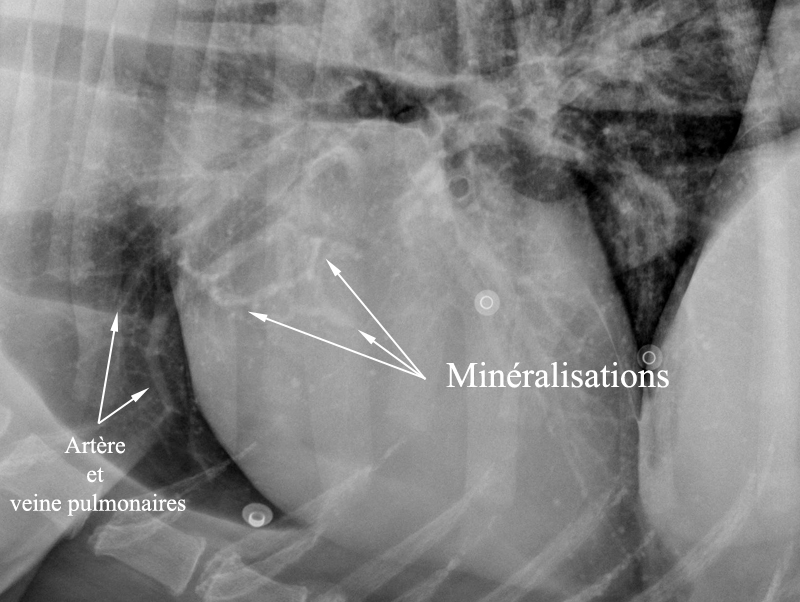

minéralisation aorte